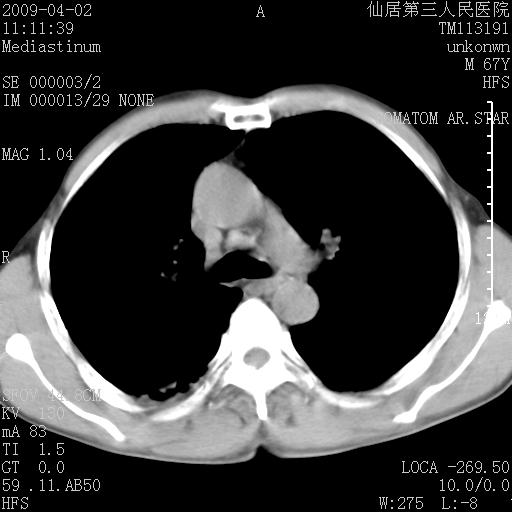

患者老年男性,乏力畏寒来诊,摄胸片示右下肺感染性病变,抗炎两周后复查胸片,无好转有进展。

后做ct平扫表现如下:

病灶呈蜂窝征,纵隔多个淋巴结肿大;肺泡癌需考虑

我认为普通的感染应该可以除外,间质性肺炎可能性较大,但如何解释纵膈的淋巴结肿大呢